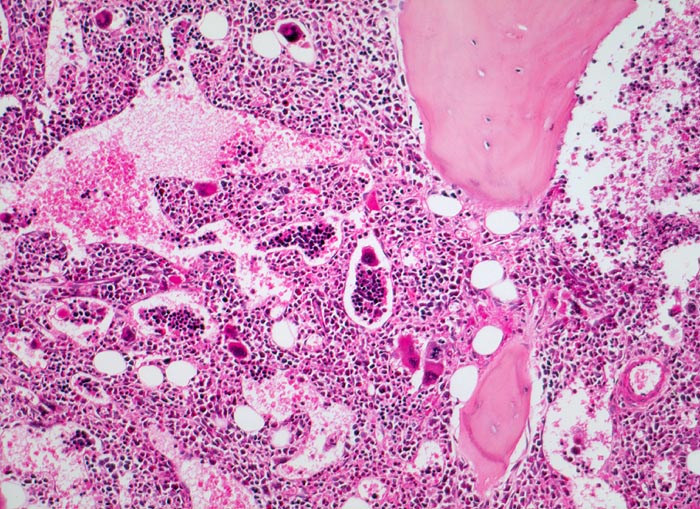

Primäre Myelofibrose (PMF)

Knochenmark, Beckenkamm

Hyperplastisches Mark mit fast vollständiger Verdrängung des Fettmarks. Typisch ist der Nachweis von Blutbildungsherden und Megakaryozyten in erweiterten Marksinus.

Splenomegalie, leichte Anämie, Leukozytose und Thrombozytose festgestellt bei einer Routineuntersuchung bei asymptomatischer Patientin.

100